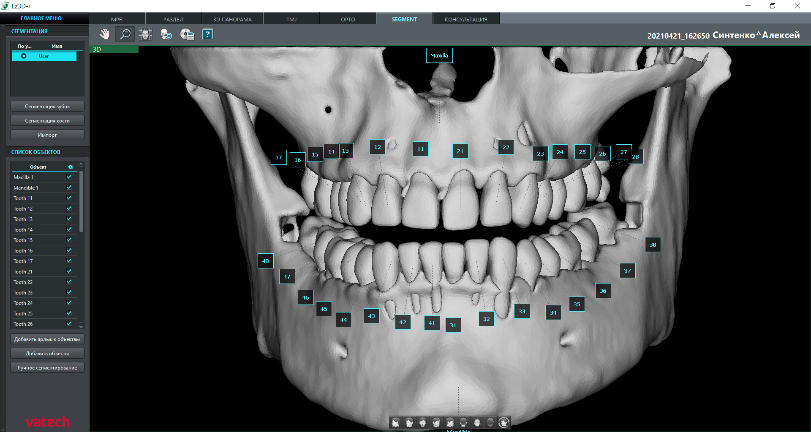

Сегментация зубов и костей

Автоматическое отделение зубов от костей и тела нижней челюсти от верхней челюсти выполняется модулем Segment. При необходимости данные о поверхности можно экспортировать* из программы Ez3D-i в виде отдельных файлов STL.

* При экспорте исследования в программу просмотра данные КТ записываются на диск вместе с моделями зубов и челюстей.

Сегментация зубов

Сегментация кости